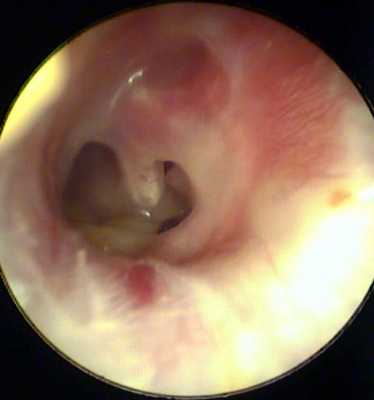

При отоскопии были выявлены достаточно характерные изменения, описанные еще L. Wallmer [6]:

Правое ухо: в наружном слуховом проходе умеренное количество водянисто-мутного отделяемого, кожа слухового прохода истончена, бледная, барабанная перепонка с тотальной центральной перфорацией, остатки барабанной перепонки обозримы по всей окружности без сформированного омозолелого края, наковальне-стремечковое сочленение скрыто навесом, рукоятка молоточка представляется укороченной, слизистая оболочка медиальной стенки утолщенная, отечная, бледная. Чувствительность слизистой оболочки практически отсутствует.

Левое ухо: в наружном слуховом проходе умеренное количество мутного отделяемого, кожа наружного слухового прохода атрофична с пониженной чувствительностью. Левая барабанная перепонка имела хорошо описанные, но прежде не иллюстрированные двойные перфорации без сформированных омозолелых краев — одна в задних отделах в пределах квадранта, вторая в передненижнем квадранте барабанной перепонки (рис. 1, на цв. вклейке). Сквозь перфорации визуализируются край наковальне-стремечкового сочленения и утолщенная пастозная слизистая оболочка медиальной стенки барабанной перепонки.

Рис. 1. Отоэндоскопическая картина.

AS — левое ухо, AD — правое ухо. Черными линиями выделены контуры костного барабанного кольца; синими — границы перфорации; красными — слуховые косточки.